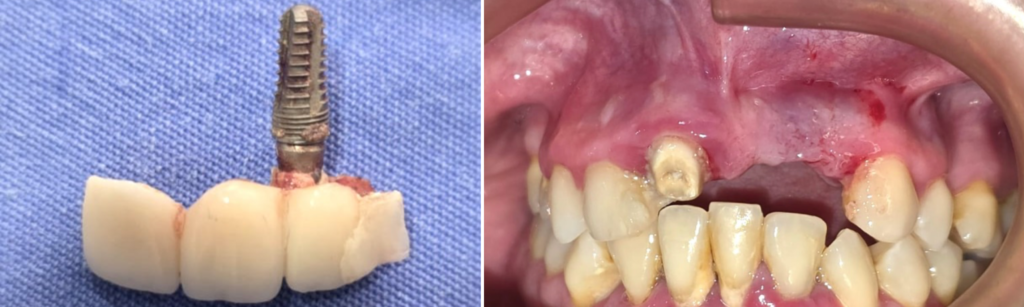

Nuestro paciente llegó a nosotros con un implante convencional fracasado en la zona anterosuperior (una de las más críticas para la estética de la sonrisa). Tras visitar varios dentistas, el diagnóstico era siempre el mismo: no existía posibilidad de colocar otro implante en el mismo lugar. La única alternativa que le ofrecían era una prótesis removible, una solución poco estética e incómoda.

El diagnóstico fue periimplantitis severa. Esta enfermedad infecciosa afecta a los implantes convencionales y provoca una destrucción progresiva del hueso que los sujeta. Como se puede apreciar en las imágenes 3D de nuestro diagnóstico, no quedaba hueso en contacto con el implante, que se mantenía en boca únicamente porque estaba cementado a un diente natural vecino.

Tras la extracción (explantación) del implante afectado y una minuciosa desinfección del área, nuestro implantólogo con amplia experiencia en técnicas avanzadas, colocó 3 implantes monofásicos córticobasales en solo 30 minutos.